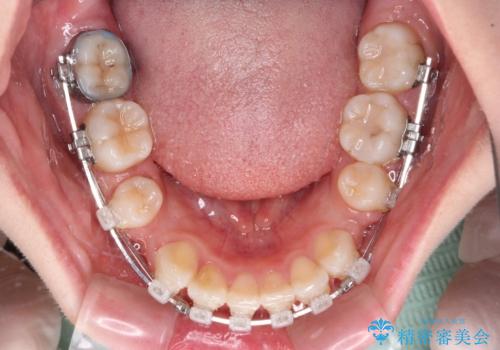

- 矯正装置

- クリアブラケット

- 前歯の出っ歯と口元の閉じにくさを気にして来院された患者様です。

口元を積極的に引っ込めるために、上下左右の小臼歯4本を抜歯することとしました。